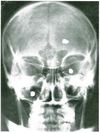

What are the bones that make up the skull and facial skeleton?

Skull (8):

Facial skeleton (15):

What are the sutures of the skull and what are the joining points you need to know?